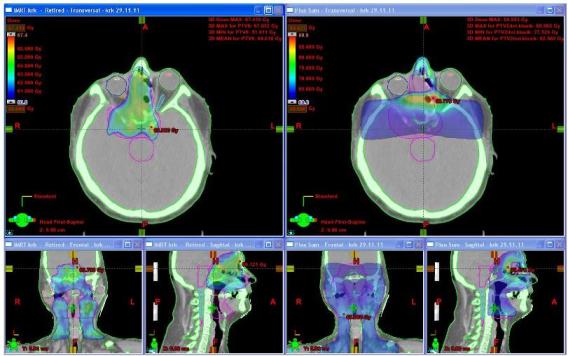

Obr. č. 1: Distribuce dávky (60 Gy a více) v transverzálním skenu v oblasti horních krčních uzlin a ve frontální a sagitální rekonstrukci u techniky IMRT (vlevo) a u 3DCR (vpravo).

Na frontální rekonstrukci plánu pro IMRT (obr. č. 1 vlevo) je patrné dobré pokrytí tumoru v oblasti vnitřní orbity vpravo a přilehlé nosní dutiny zvolenou dávkou na rozdíl od 3DCR (obr. č. 1 – vpravo), kde je toto pokrytí nedostatečné. Na frontálních i sagitálních rekonstrukcích (obr. č. 1 vlevo) v barevném mapování dávky je vidět eskalovanou dávku v místech tumoru (zelená barva).

Obr. č. 2: Distribuce dávky (63 Gy a více – zelená, 60 Gy a více modrá ) v transverzálním skenu v oblasti orbity, dutiny nosní a sfenoidální, ethmoidů a ve frontální a sagitální rekonstrukci u techniky IMRT (vlevo) a u 3DCR (vpravo).